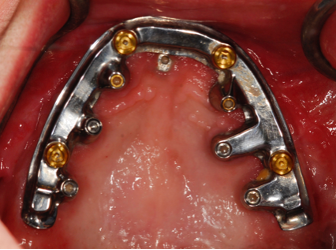

(42.) Fixed-removable prosthesis.

Figure 42

(43.) Fixed-removable prosthesis.

Figure 43

(44.) Fixed-removable prosthesis.

Figure 44

(45.) Fixed-removable prosthesis.

Figure 45

At the initial patient examination, several factors in addition to restoration shape should be considered when planning implant-supported restorations. History of periodontal disease, irregular maintenance visits, clinical appearance of the remaining teeth and soft tissue conditions may indicate increased risk of peri-implantitis. Patient dexterity, adaptability, willingness, and capability to carry out intended home care should be considered. Patient's mental conditions including dementia may influence the design of this as well as unrealistic patient expectations. A "High water original Branemark design" or no treatment may be indicated. Especially when implant location makes access, a fixed-removable design may be necessary to reduce risk of peri-implantitis may be indicated (Figures 42 through Figure 45). Considering that oral biofilm accumulation, even at two weeks post prosthetic insertion is documented, periodic removal of screw retained restorations is less effective than daily access to disrupt bacterial plaque accumulation.